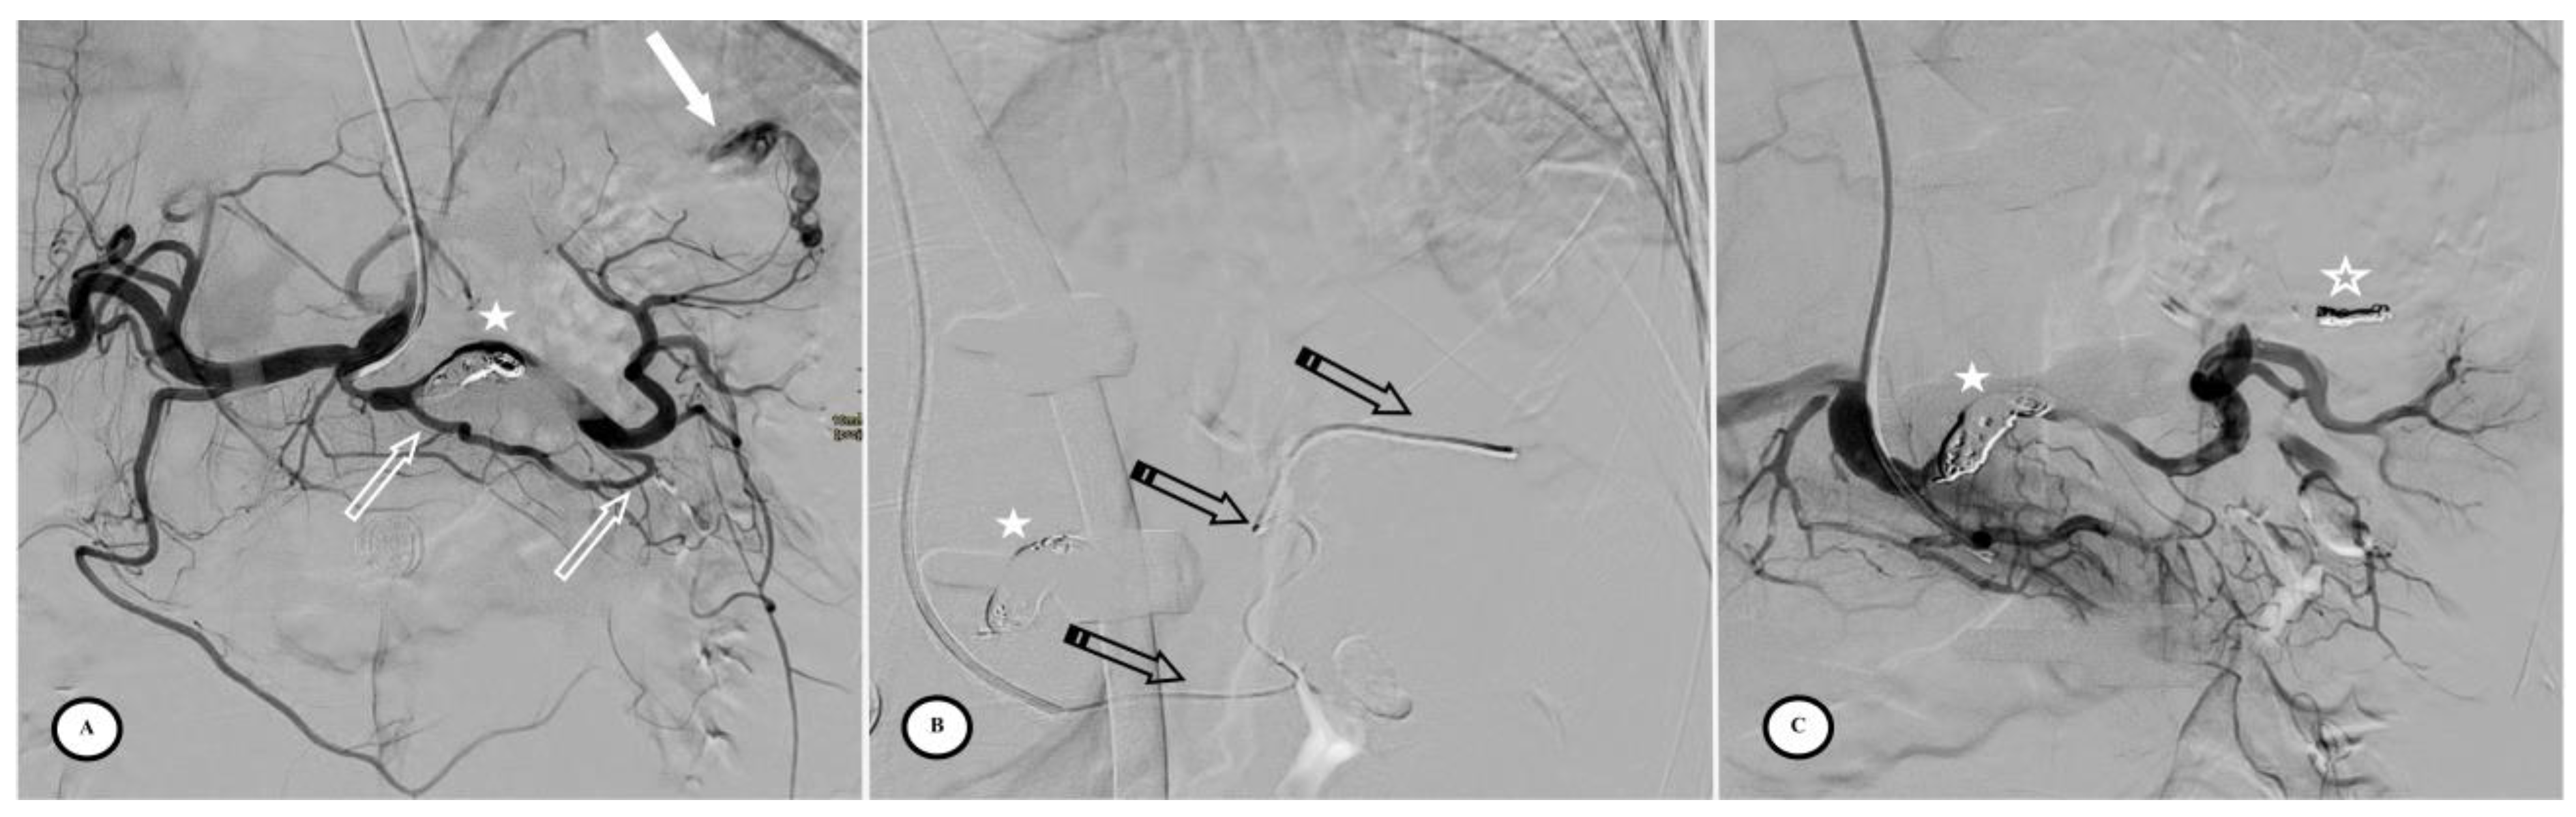

Selective angiographic images during the splenic artery embolization Coil Embolization To Pseudoaneurysm Of Splenic Artery Splenic artery pseudoaneurysms are even more rare than true aneurysms. embolization is a valuable alternative to surgical management in splenic artery psa. The purpose of this article is to define the role of splenic embolization in trauma patients and in patients presenting. distal artery embolization and embolization of the pseudoaneurysm. percutaneous embolization appears to be the best. Coil Embolization To Pseudoaneurysm Of Splenic Artery.

Angiography after selective catheterization of the splenic artery (a Coil Embolization To Pseudoaneurysm Of Splenic Artery distal artery embolization and embolization of the pseudoaneurysm. if there is a single pseudoaneurysm, coil/plug embolization of the pseudoaneurysm can be performed with embolization distal (outflow; embolization is a valuable alternative to surgical management in splenic artery psa. Splenic artery pseudoaneurysms are even more rare than true aneurysms. percutaneous embolization appears to be the best method. Coil Embolization To Pseudoaneurysm Of Splenic Artery.